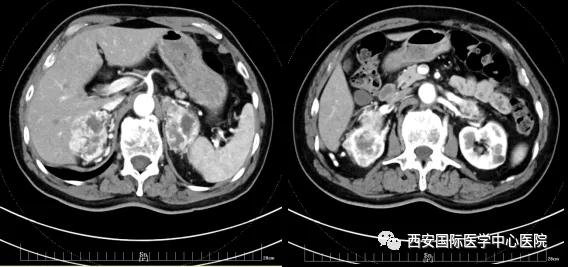

今年七十五歲的患者,來自陜西省商洛市,四月前因腰背部疼痛就診于當(dāng)?shù)蒯t(yī)院,行CT檢查發(fā)現(xiàn)“右腎、雙側(cè)腎上腺占位,前縱膈淋巴結(jié)腫大,雙肺多發(fā)結(jié)節(jié)、胸椎骨質(zhì)破壞,考慮轉(zhuǎn)移瘤”。為進(jìn)一步診斷治療,患者的兒子帶他來到西安某三甲醫(yī)院,查泌尿系CT提示“右腎占位性病變,多考慮腎癌,雙側(cè)腎上腺多發(fā)轉(zhuǎn)移灶,腹膜后多發(fā)腫大淋巴結(jié)”;行穿刺活檢提示“腎透明細(xì)胞癌”;并給予患者口服靶向藥物的治療方案。

自四月份至今,患者一直口服靶向藥物治療(阿昔替尼5mg 2次/日),期間無不良反應(yīng),目前腰背部疼痛癥狀也有所緩解,復(fù)查影像學(xué)資料提示瘤體較前縮小,腫瘤完整切除的可能性明顯提高;而且患者的兒子也是一名外科醫(yī)生,所以他更想為父親完成后續(xù)的手術(shù)治療。

患者一家慕名前來到西安國(guó)際醫(yī)學(xué)中心醫(yī)院找到楊增悅教授。楊增悅教授仔細(xì)看完患者的之前的影像學(xué)及病理資料后,診斷為:右腎透明細(xì)胞癌(T4N1M1);并安排他住院。而后,主管醫(yī)生及時(shí)為他完善了術(shù)前檢查及評(píng)估。7月15日,在麻醉手術(shù)中心柴偉主任、王彬榮副主任、李娟護(hù)士長(zhǎng)、李瑞剛護(hù)士長(zhǎng)及全體麻醉手術(shù)中心團(tuán)隊(duì)的有力保障下,成功完成了這臺(tái)“大”手術(shù)。

手術(shù)由楊增悅教授主持,舒濤主治醫(yī)師、王東主治醫(yī)師主刀,黃怡醫(yī)師、王平醫(yī)師協(xié)助完成。由于第四代達(dá)芬奇機(jī)器人更加靈活和精準(zhǔn)的特性,手術(shù)全程順利,尤其是完全精準(zhǔn)的“解鎖”了右腎動(dòng)脈和右腎靜脈的數(shù)十根交互纏繞的分支血管。術(shù)后患者麻醉恢復(fù)后生命體征平穩(wěn),順利返回泌尿外科普通病區(qū)進(jìn)一步康復(fù)。